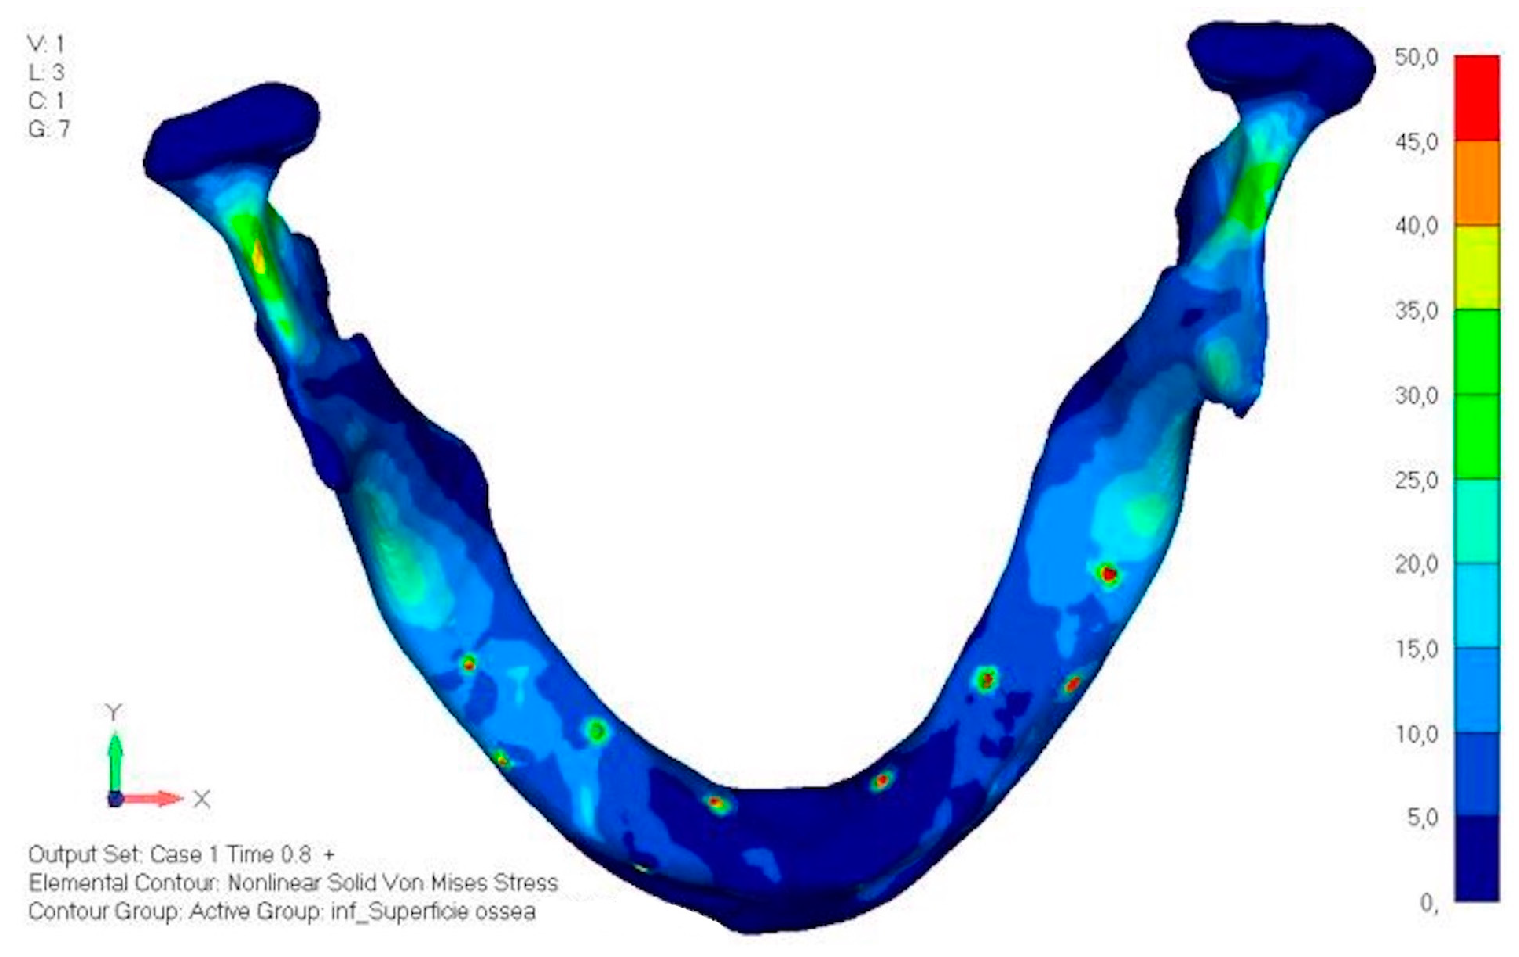

- Model V0. This model represents the initial analysis performed on the lower arch. The implant consists of two completely separate hemi-arches. The situation observed in the lower model is very similar to that found in the upper model. The most significant load is load 3 (Figure 20a,b), corresponding to chewing in the anterior right sector. Loads distributed over larger areas, such as configurations 1 and 2, result in less stress on both the implant and the bone (Figure 21 and Figure 22).

- Even in the lower model, the stresses observed in the peri-implant bone are always acceptable and significantly lower compared to those found in the upper implant. In the worst case, peak stresses reached 250 MPa, which ensures an adequate safety margin. From the bone perspective, in load configuration 3, it is noted that stresses exceed 50 MPa even in areas distant from the implant, such as near the condyles and in the posterior alveolar process.